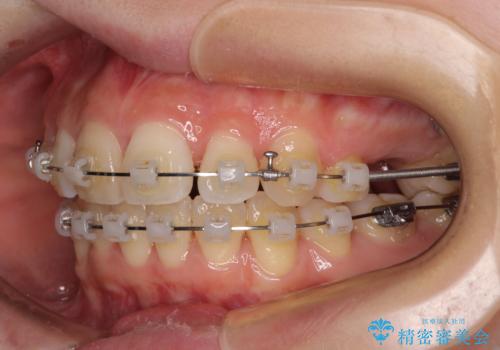

- 奥歯の欠損と、抜歯矯正の後戻りを気にして来院された患者様です。

上下前歯をワイヤー保定していましたが、強い舌の突出癖により上下ともにスペースができ、上下前歯は非接触になっていました。

マウスピース矯正でもワイヤー矯正後でも対応可能でしたが、自己管理の煩わしさからワイヤー矯正後を選択されました。

舌のトレーニングをしっかりと行っていただきながらワイヤー装置により矯正治療を行い、途中でインプラントを埋入し、矯正治療後に補綴治療を行うこととしました。

舌の突出癖を改善したことで、突出感のあった口元の印象も、やや引っ込めることができました。